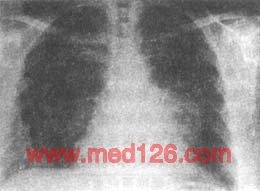

图1胸腺瘤

胸部平片;正位像显示左心缘旁团块影